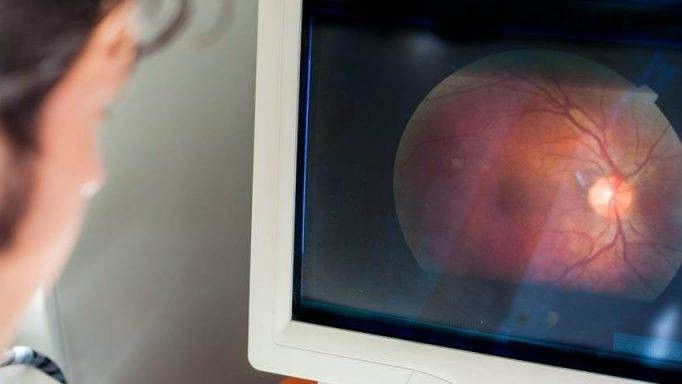

Infarkti i syve – si ndodh dhe si ta dallojmë atë?

Infarkti i syrit ndodh për shkak të bllokimit të plotë të enëve të gjakut që furnizojnë nervin optik dhe mungesës së presionit. Presioni i gjakut ndryshon në raport presionin e syrit dhe ka një rënie të qarkullimit të gjakut.